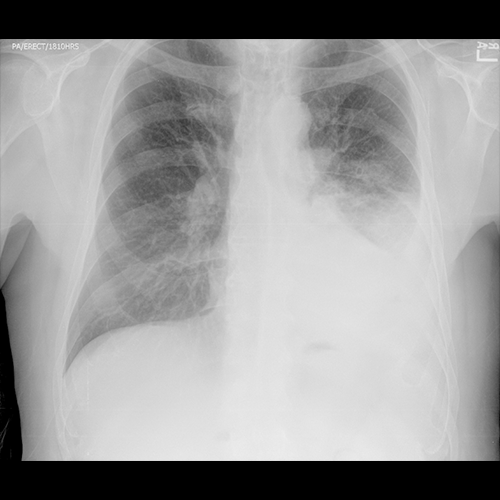

Chest X-ray

What best describes the findings on the Chest X-ray?

This chest X-ray is most consistent with a pleural effusion as the left costophrenic angle is obscured. There likely are also airspace opacities in the left lower lung indicating the underlying pneumonia.

View the full study if you'd like to take a look yourself.

Sometimes, X-ray can strongly suggest the presence of a complicated pleural effusion or empyema, where it forms an obtuse angle with the chest wall and has a lenticular, biconvex shape. These findings are not evident on the radiographs. Considering the strong clinical suspicion, we should obtain a CT for further evaluation. Chest CT with contrast is preferred for evaluation of pleural effusion or empyema.